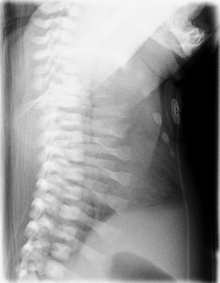

Lateral CXR of the same person above.